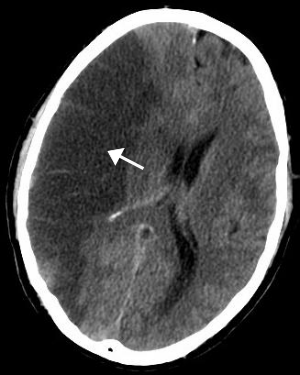

CT scan of the brain showing a right-hemispheric ischemic stroke.

CT scan of an intraparenchymal bleed (bottom arrow) with surrounding edema (top arrow)